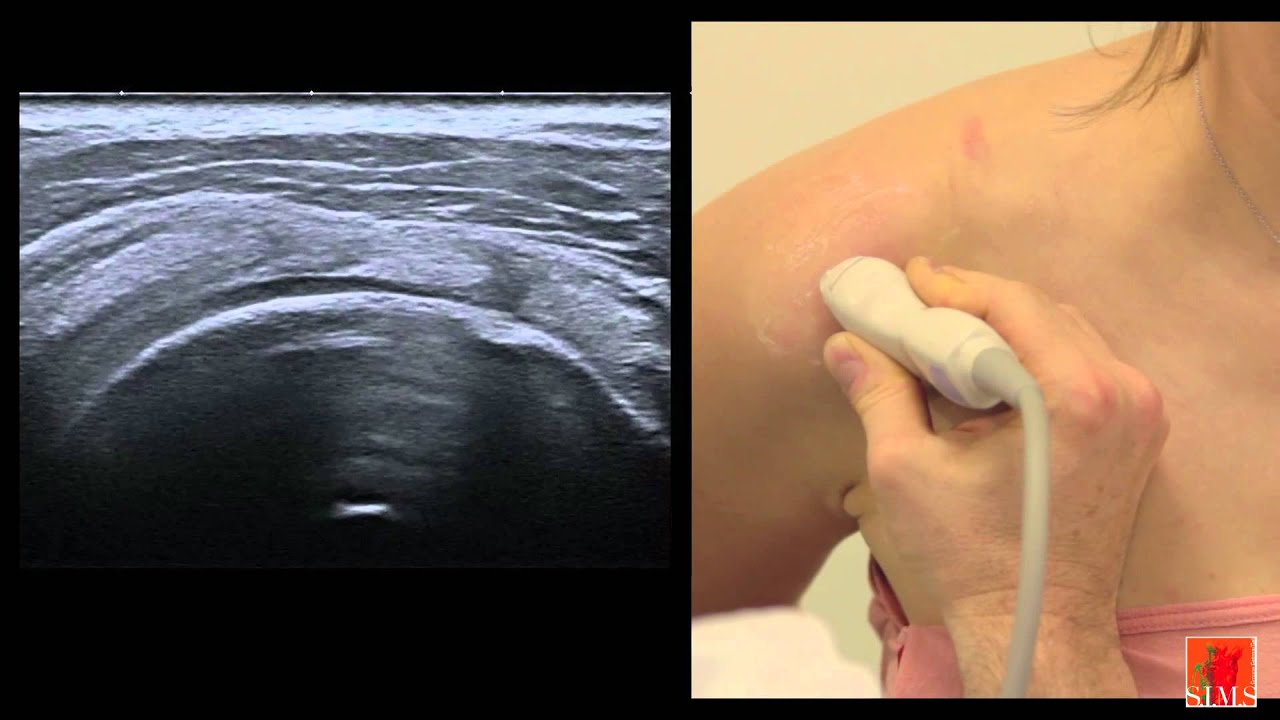

Échographie de l'épaule II

Описание: Échographie de L'épaule Démonstration Pratique

Chapitre II: La région antérosupérieure

SIMS ultrasound academy